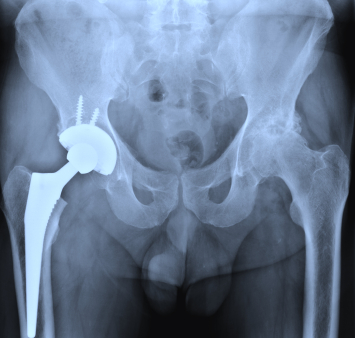

Артрография осуществляется наметить суставы и связки. Краситель вводится в сустав и рентгеновские лучи приняты с целью выявления любых травм.